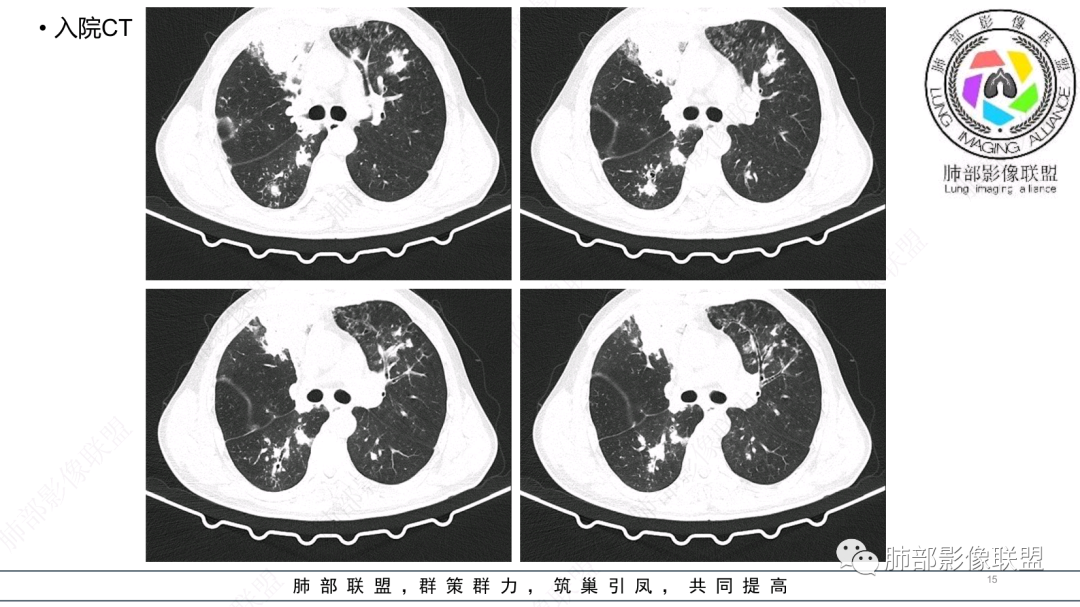

中老年男性,发病一周,发热,炎症指标明显增高,双肺支气管扩张基础,双肺可见多发结节、斑片状、团块状密度增高,边缘尚清。病灶分布与支气管关系密切,考虑支扩合并感染,铜绿,NTM、奴卡、曲霉等,环卫工人,可能接触腐败物较多,考虑曲霉可能大,鉴别奴卡。

男性,56岁,清洁工,临床表现咳嗽咳痰发热。胸部影像:两肺散在斑片、结节及实变影,大部分沿气道分布,以下肺为著并伴发多发支气管扩张及囊腔影,实验室检查白细胞增高,考虑感染性病变,曲霉、铜绿及NTM。

56岁,工作性质:环卫工人。主诉:咳、痰、喘、发病一周。急性起病(或者慢病+AE),呼吸道感染症状。化验指标白细胞、中性、CRP明显升高。影像学显示多灶性,有柱状支扩,囊状支扩等结构肺病,责任细菌主要考虑铜绿假单胞菌,不排除合并其他细菌以阴杆为主;存在树芽影,发热,炎症沿支气管束分布,是否合并TB?真菌?;树芽伴发热支原体感染也要需要考虑进去;全肺多灶性炎症,部分病灶周围有晕,右上叶疑似反晕,内部疑似有丝,右下肺考虑存在粘液栓,加之环卫工工作性质,考虑霉菌,主要考虑曲霉。

两肺支扩,两肺沿支气管分布多发结节、树芽及团块,边缘模糊,部分支气管管壁增厚,考虑气道侵袭性曲霉菌,鉴别铜绿、奴卡、结核。

支气管壁增厚,晕征明显,病灶沿着支气管纵向分布,结合患者职业,考虑气道侵袭性曲霉。

多发结节,部分结节边缘清楚,部分边缘模糊,支扩合并肉芽肿性炎,奴卡菌与曲霉之间选择。

CT:双肺延支气管血管束分布斑片状、团块状、树芽状密度增高影,部分边界模糊,支气管扩张、部分管壁增厚。考虑气道吸入细菌性感染,铜绿假单孢?